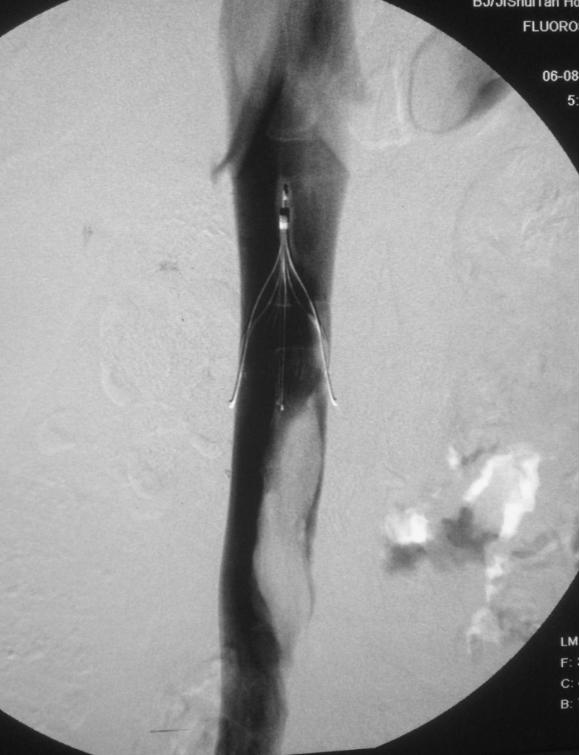

近年来,随着介入诊疗技术的进步,更为积极的治疗措施越来越多。比如,当发现静脉内血栓负荷比较大,单纯抗凝治疗效果不佳,或有过高的出血风险,或可能遗留“血栓形成后综合征”,介入医生无须切开,只需穿刺静脉,就可在几分钟内完成“下腔静脉滤器植入术”,即于人体内最宽大的静脉内植入“过滤器”,将脱落的血栓拦住,但不影响血液回流,肺栓塞的风险就可有效地避免。

下腔静脉内植入了滤器,拦阻到巨大血栓

在植入滤器的基础上,介入医生可立即插管到血栓局部进行机械或人工方法抽栓、取栓、溶栓,还能对诱发血栓的某些病变(如腔内粘连、髂静脉压迫等)进行扩张松解、支架植入等针对性治疗,从而消除将来复发的风险。